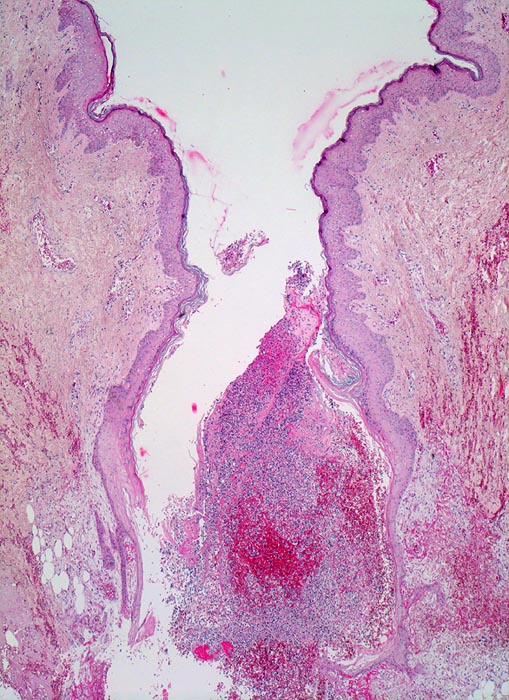

• Schlitzförmiger, bis in die Subkutis reichender Hautdefekt.

• Neugebildete Epidermis bedeckt im oberen intradermalen Anteil des Wundspaltes teilweise den Gewebsdefekt.

• Daran angrenzender Wundspalt im Bereich des subkutanen Fettgewebes mit Fibrinauflagerungen und ödematösem zellarmem Granulationsgewebe.

• An der Basis des Präparates Auseinanderklaffen des Wundspalts wegen grösserem Blutkoagel (verursacht Wundheilungsstörung).